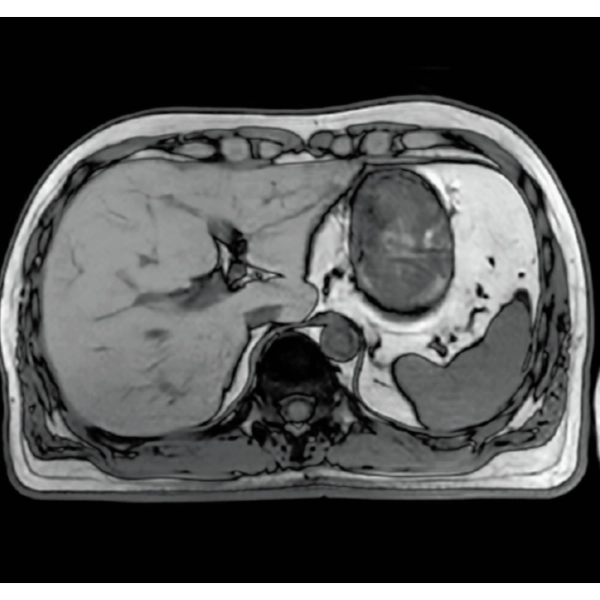

Imperfect imaging data to be better image quality through post-processing

By providing functions to remove and suppress artifacts in the imaging data and to generate reconstructed images from limited imaging data, it reduces the re-imaging rate and supports the realization of smooth MRI examinations.

Reduce artifacts caused by patient movement, such as coughing or sneezing, by post reconstruction.

Improving SNR and reducing wrap-around artifact through post reconstruction.

Even if the examination is interrupted, the minimum necessary data can be reconstructed later.

When motion artifacts occurs in the image due to coughing, sneezing, or involuntary movements, either or both the visual information acquired by monitoring cameras, Synergy Vision, and the intrabody information acquired by the navigator pulse can be used to provide an image with reduced artifacts. This reduces the re-imaging rate.

Body movements that affect image quality are detected from monitoring cameras based on thresholds derived for each body part.

Movements within the body are detected by navigator pulses. Body movements that significantly affect image quality are detected based on the error between pulses.

Deep Learning technology*8 enables image quality adjustment after imaging is complete. It optimize SNR and improve image sharpness by processing MRI signals in stages (k-space signal processing). This brings super-resolution and reduces truncation artifacts.

When the size in the phase encoding direction is incorrectly set , the signal outside the FOV will fold back and appear as artifacts in the image. Exp. RAPID reconstructs the image according to the specified FOV magnification ratio. Artifacts can be removed in post-processing.